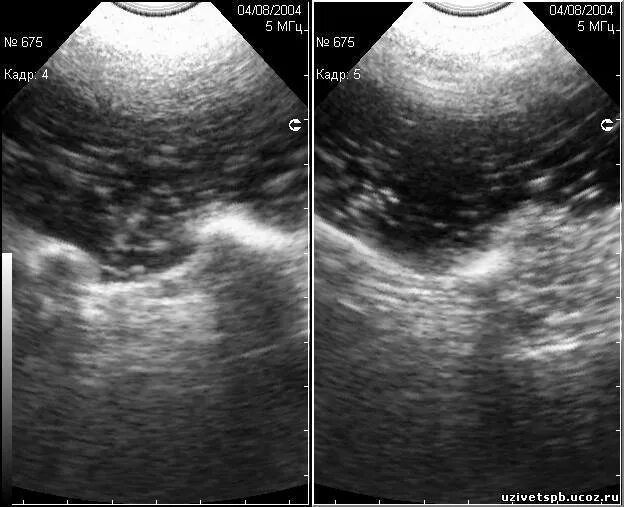

Как выглядит узи живота